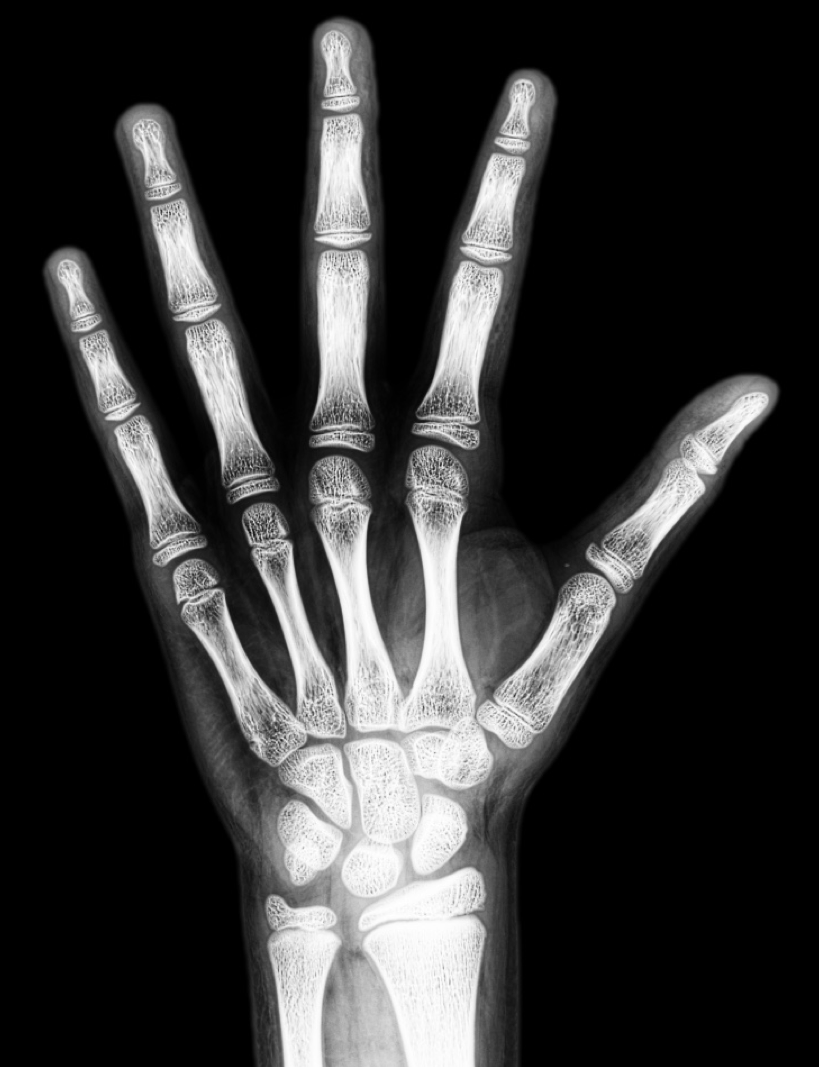

Kemik yaşı tayini için çekilen el bilek grafisi, çocuğunuzun iskelet sisteminin olgunluğunun belirlenmesinde önemli bilgiler verir. Genellikle sol el, bilek ve el parmaklarının içerecek şekilde tek bir röntgen filmi çekilerek yapılır. Çocuğunuzun sağlığı için herhangi bir risk oluşturmayacak düzeyde, çok az miktarda radyasyon kullanılan güvenli ve ağrısız bir tetkiktir. İşlem sırasında bu çok az miktardaki radyasyonun olumsuz olabilecek etkilerini de engellemek için tiroid bezi ve yumurtalık gibi hassas organlar kurşun koruyucu önlüklerle korunmaktadır. İşlem için herhangi bir ön hazırlık gerekmemektedir. Oldukça hızlı şekilde birkaç saniye içerisinde film çekimi gerçekleştirilir. Çekim süresince, çocuğun elinin parmaklar açık şekilde inceleme masasında hareketsiz kalması çekim kalitesi için oldukça önemlidir.

Bir çocuğun parmak ve el bileğindeki kemiklerin heriki ucunda büyüme plağı adı verilen büyüme alanları bulunur. Bu plaklar kemiklerin uzunlama büyümesini sağlayan özel hücrelerden oluşur. Büyüme plakları daha az mineral içerdiklerinde, röntgen görüntüsünde kemiğin diğer kesimlerine göre daha siyah olarak görünürler. Bu nedenle röntgen filmlerinde ayırt edilmeleri oldukça kolaydır. Çocuklar büyüdükçe, bu büyüme plaklarının X - ışını görüntüleri değişir ve tedricen incelerek en sonunda kaybolur, yani büyüme plağı kapanır. Her yaşta kemiklerin ve büyüme plaklarının görünümü farklıdır.

Röntgen filmindeki kemiklerin gelişim düzeyi aynı cinsiyet ve yaştaki çok sayıda çocuktan elde edilmiş verilerle oluşturulmuş standart bir kemik yaşı atlasındaki el grafileri ile karşılaştırılır.

Tanner – Whitehouse 2 yöntemine göre ön kol, el bilek ve parmak kemiklerinin gelişimi  ayrı ayrı tablolarla değerlendirilerek çocuğun kemik yaşı tayin edilir.

Kliniğimizde radyolojik çekimi yapılmış el bileği grafisi